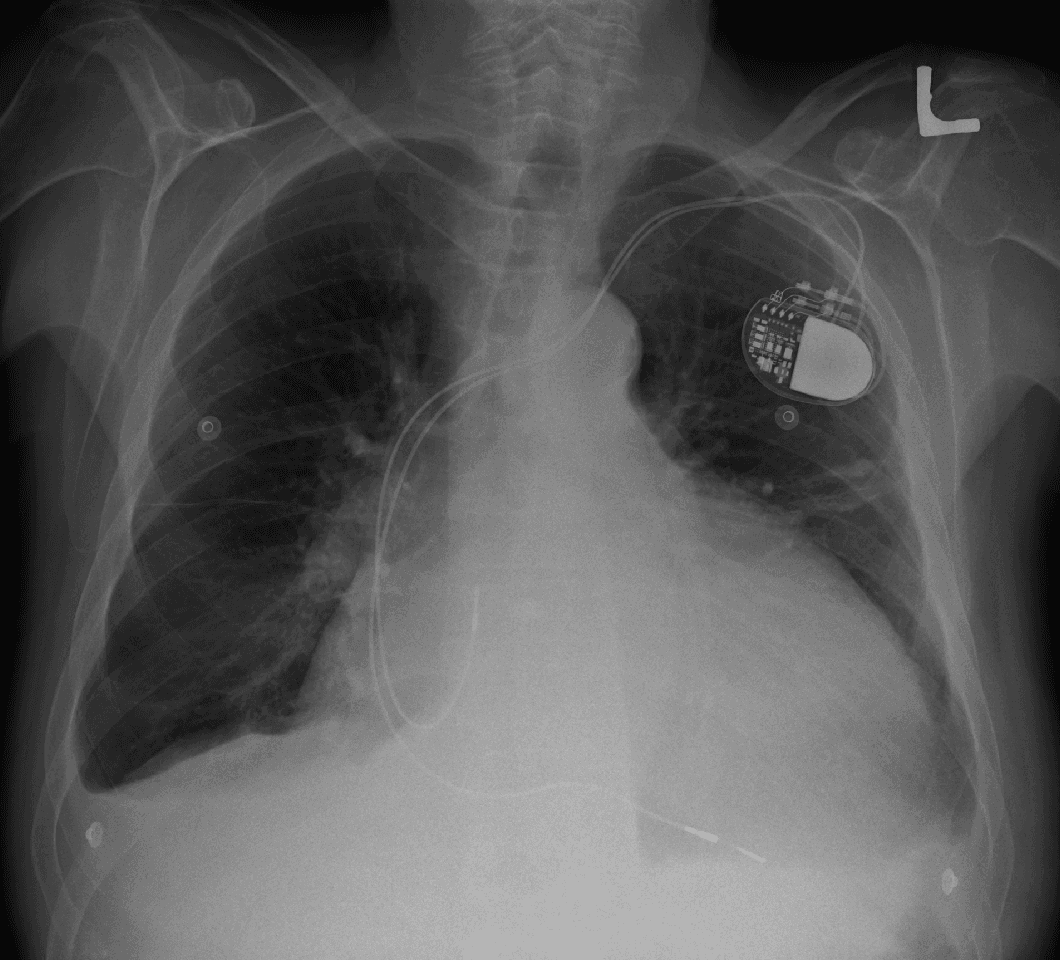

Cardiomegaly (sometimes megacardia or megalocardia) is a medical condition in which the heart becomes enlarged. It is more commonly referred to simply as "having an enlarged heart". It is usually the result of underlying conditions that make the heart work harder, such as obesity, heart valve disease, high blood pressure (hypertension), and coronary artery disease. Cardiomyopathy is also associated with cardiomegaly. Cardiomegaly can be serious and can result in congestive heart failure. Recent studies suggest that cardiomegaly is associated with a higher risk of sudden cardiac death. Cardiomegaly may diminish over time, but many people with an enlarged heart (dilated cardiomyopathy) need lifelong medication. Having a family history of cardiomegaly may indicate an increased risk for this condition. Lifestyle factors that can help prevent cardiomegaly include eating a healthy diet, controlling blood pressure, exercise, medications, and not abusing alcohol and cocaine. For many people, cardiomegaly is asymptomatic. For others, if the enlarged heart begins to affect the body's ability to pump blood, then symptoms associated with congestive heart failure may arise, including: Heart palpitations – the irregular beating of the heart, usually associated with a valve Severe shortness of breath (especially when physically active) Chest pain Coughing, when lying down Fatigue Leg swelling Increased abdominal girth Weight gain Edema – swelling Fainting The causes of cardiomegaly are not well understood and many cases have no known cause. Lifestyle-related risk factors include tobacco use and high cholesterol, high blood pressure, and diabetes. Non-lifestyle risk factors include a family history of cardiomegaly, coronary artery disease (CAD), congenital heart failure, atherosclerotic disease, valvular heart disease, exposure to cardiac toxins, sleep-disordered breathing (such as sleep apnea), sustained cardiac arrhythmias, abnormal electrocardiograms, and cardiomegaly on chest X-ray.